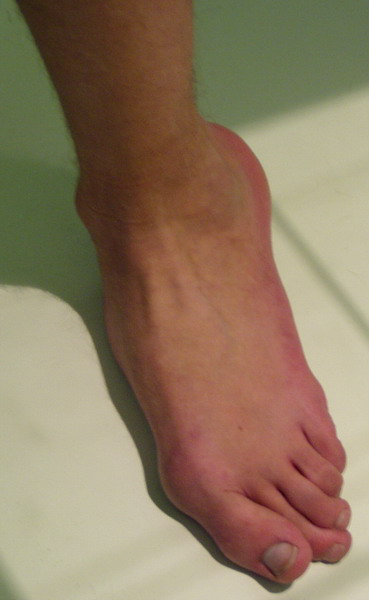

Пациент 15 л., болезнь Литтля, спастический нижний парапарез, интеллект высокий. Ребенок настроен на активный образ жизни. С недавнего времени начал ходить без дополнительной опоры. Появилась проблема с левой стопой - во время ходьбы опора приходится на смещенную кнутри таранную кость.

Может образоваться болезненный натоптыш или язва.Общепринятой операцией является трехсуставной артроде с мобилизацией таранной кости. Выполнять такую операцию у спастика и в раннем возрасте проблематично. Родстьвенники тем более готовы материально и морально осуществить хирургическое лечение за рубежом, если оно показано и возможно.Предпочтительно в Австрии и Германии. Если кто-то посоветует координаты таких клиник - были бы признательны.

Это типичная проблема со стопами у больных спастическим церебральным параличом. У Вашего пациента ситуация несколько запущена. Но решать её надо.

В приводимом случае, 15 летнему больному показан 3-суставной артродез. Однако считаю нецелесообразным существенно менять конфигурацию стопы, поскольку плоско-вальгусные деформации стоп это компенсаторный ответ на сгибательно-приводящие установки нижних конечностей. Изменение положения стоп(коррекция пронации) может нарушить сложившийся стереотип ходьбы, и ухудшить ситуацию.